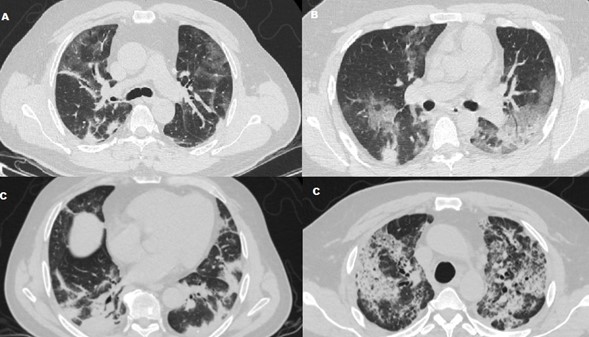

According to the tomographic findings (Figure 1), the predominant pattern was the mixed pattern (n = 26, 36.6%), and other common findings included ground glass pattern (GGO) (n = 25, 35.2%), followed by the crazy pattern paving (n = 15, 21.1%) and pulmonary consolidation (n = 5, 7.0%). Some of the related characteristics of the chest tomography were found as follows: subpleural lines (n = 25, 35.2%), lymphadenopathy (n = 20, 28.1%), fibrosis (n = 13, 18.3%), pleural effusion (n = 11, 15.4%), and inverted halo sign (n = 2, 2.8%). Pulmonary tomographic lesions were found with higher frequency bilaterally (n = 64, 90.1%), subpleural distribution (n = 61, 85.9%), and in the lower lobes (n = 31, 43.6%) (Table 2).

The degree of involvement using the semi-quantitative measurement of the extent of lesions by pulmonary lobes was classified into mild involvement (62.7%), moderate involvement (21.5%), and severe involvement (15.6%). GGO was significantly more prevalent in mild (15 patients, 21.1%, p < 0.001) compared to moderate (nine patients, 12.6%) and severe (one patient, 1.4%), while pulmonary consolidation patterns (four patients, 5.6%; p < 0.048) and crazy paving and fibrosis (eight patients, 11.2%, p < 0.033) were significantly more common in severe affectation. There were no significant differences for the inverted halo sign, pleural effusion, and lymphadenopathy in terms of the degree of involvement (Table 3).

The characteristics of the chest tomography and the clinical classification of covid-19 according to the severity of the symptoms in this group of patients was that the GGO tomographic pattern was significantly more prevalent in the mild clinical stage (19 patients, 26.7%; p <0.001), while the crazy paving tomographic pattern (15 patients, 21.1%; p < 0.001) in the moderate clinical stage and pulmonary consolidation (three patients, 4.2%; p < 0.003) were significantly more frequent in the severe clinical stage of this group of patients (Table 4).